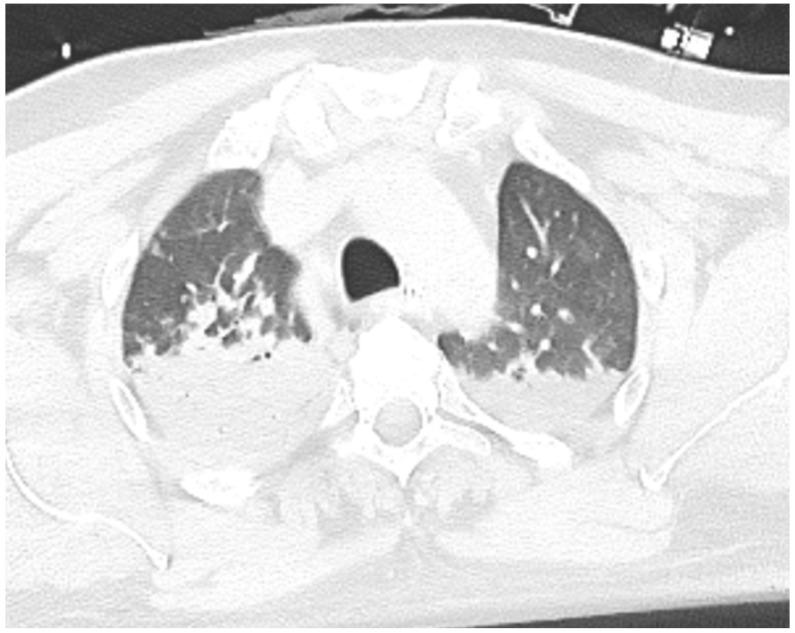

Toxic myocarditis (TM) is rare, and no systematic evidence is available regarding its treatment or prognosis. Hydrocarbons even more rarely cause TM, and they are associated with severe extracardiac toxicity. Moreover, a pathogenic interaction between viral and toxic agents in TM has not been studied. We present the first case of biopsy-proven parvovirus B19 (B19V) viral fulminant myocarditis diagnosed after hydrocarbon exposure, along with a systematic literature review of hydrocarbon-TM cases. A systematic literature review was conducted by searching hydrocarbon-TM cases. Clinical and prognostic data were recorded. After screening of 937 records, 7 were included. All cases were male, with a median age of 24 years (IQR 23-25). Chest pain and dyspnea were the main symptoms, but arrhythmic presentation was also reported; endomyocardial biopsy (EMB) was performed in only one case. Overall, treatment was based on supportive measures, such as antiarrhythmic and/or vasoactive therapy. Our example (male, 47 years old) is the first reported fulminant biopsy-proven case diagnosed after a massive exposure to hydrocarbons, in which EMB molecular analysis unexpectedly revealed B19V with a high viral load. Hemodynamic and arrhythmic instability required percutaneous stellate ganglion blockade and temporary wearable defibrillator use. Left ventricular function spontaneously normalized at 3 months. In conclusion, we report the first fulminant B19V myocarditis case temporally associated with aromatic hydrocarbon exposure due to a coexistence of viral and toxic causes. Our case and the systematic review show that promptly performing EMB can provide a definitive diagnosis and guide treatment, especially in severe cases in which infectious agents may contribute to myocardial damage.

中毒性心肌炎(TM)较为罕见,目前尚无关于其治疗或预后的系统性证据。碳氢化合物引发TM的情况更为罕见,且与严重的心外毒性相关。此外,TM中病毒与毒性因子之间的致病相互作用尚未得到研究。我们报告了首例经活检证实的细小病毒B19(B19V)暴发性心肌炎病例,该病例在接触碳氢化合物后被诊断出来,并对碳氢化合物相关TM病例进行了系统性文献综述。通过检索碳氢化合物相关TM病例进行了系统性文献综述。记录了临床和预后数据。在筛选937条记录后,纳入了7例。所有病例均为男性,中位年龄24岁(四分位间距23 - 25岁)。胸痛和呼吸困难是主要症状,但也有心律失常的表现;仅1例进行了心内膜活检(EMB)。总体而言,治疗基于支持性措施,如抗心律失常和/或血管活性治疗。我们的病例(47岁男性)是首例报道的在大量接触碳氢化合物后经活检证实的暴发性病例,其中EMB分子分析意外发现高病毒载量的B19V。血流动力学和心律失常不稳定需要进行经皮星状神经节阻滞并使用临时可穿戴式除颤器。左心室功能在3个月时自发恢复正常。总之,我们报告了首例因病毒和毒性因素共存而在时间上与芳香烃暴露相关的暴发性B19V心肌炎病例。我们的病例和系统性综述表明,及时进行EMB可提供明确诊断并指导治疗,尤其是在感染因子可能导致心肌损伤的严重病例中。